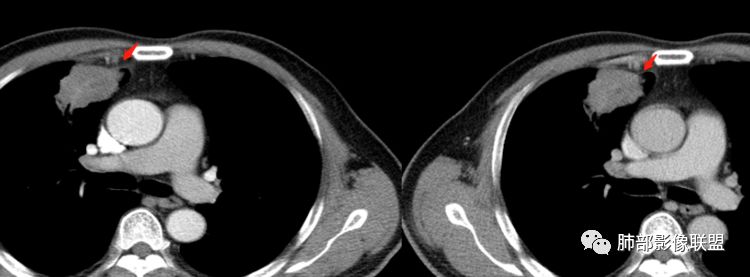

尘缘:@李双喜,阳朔县医影像科?内乳动脉增粗有意义,但不能直接鉴别良恶性,可以提示这个病灶时间比较久了,慢性炎性肉芽肿和肿瘤都可以增粗。Coke with ice:

南边:内乳的血管,没看到与病灶的关系啊。

郑氏刀刀:动脉没有增粗,静脉增粗了,静脉平滑肌薄,容易扩张。这样的边缘炎性一定有

南边:这个连续的,可能是血管。